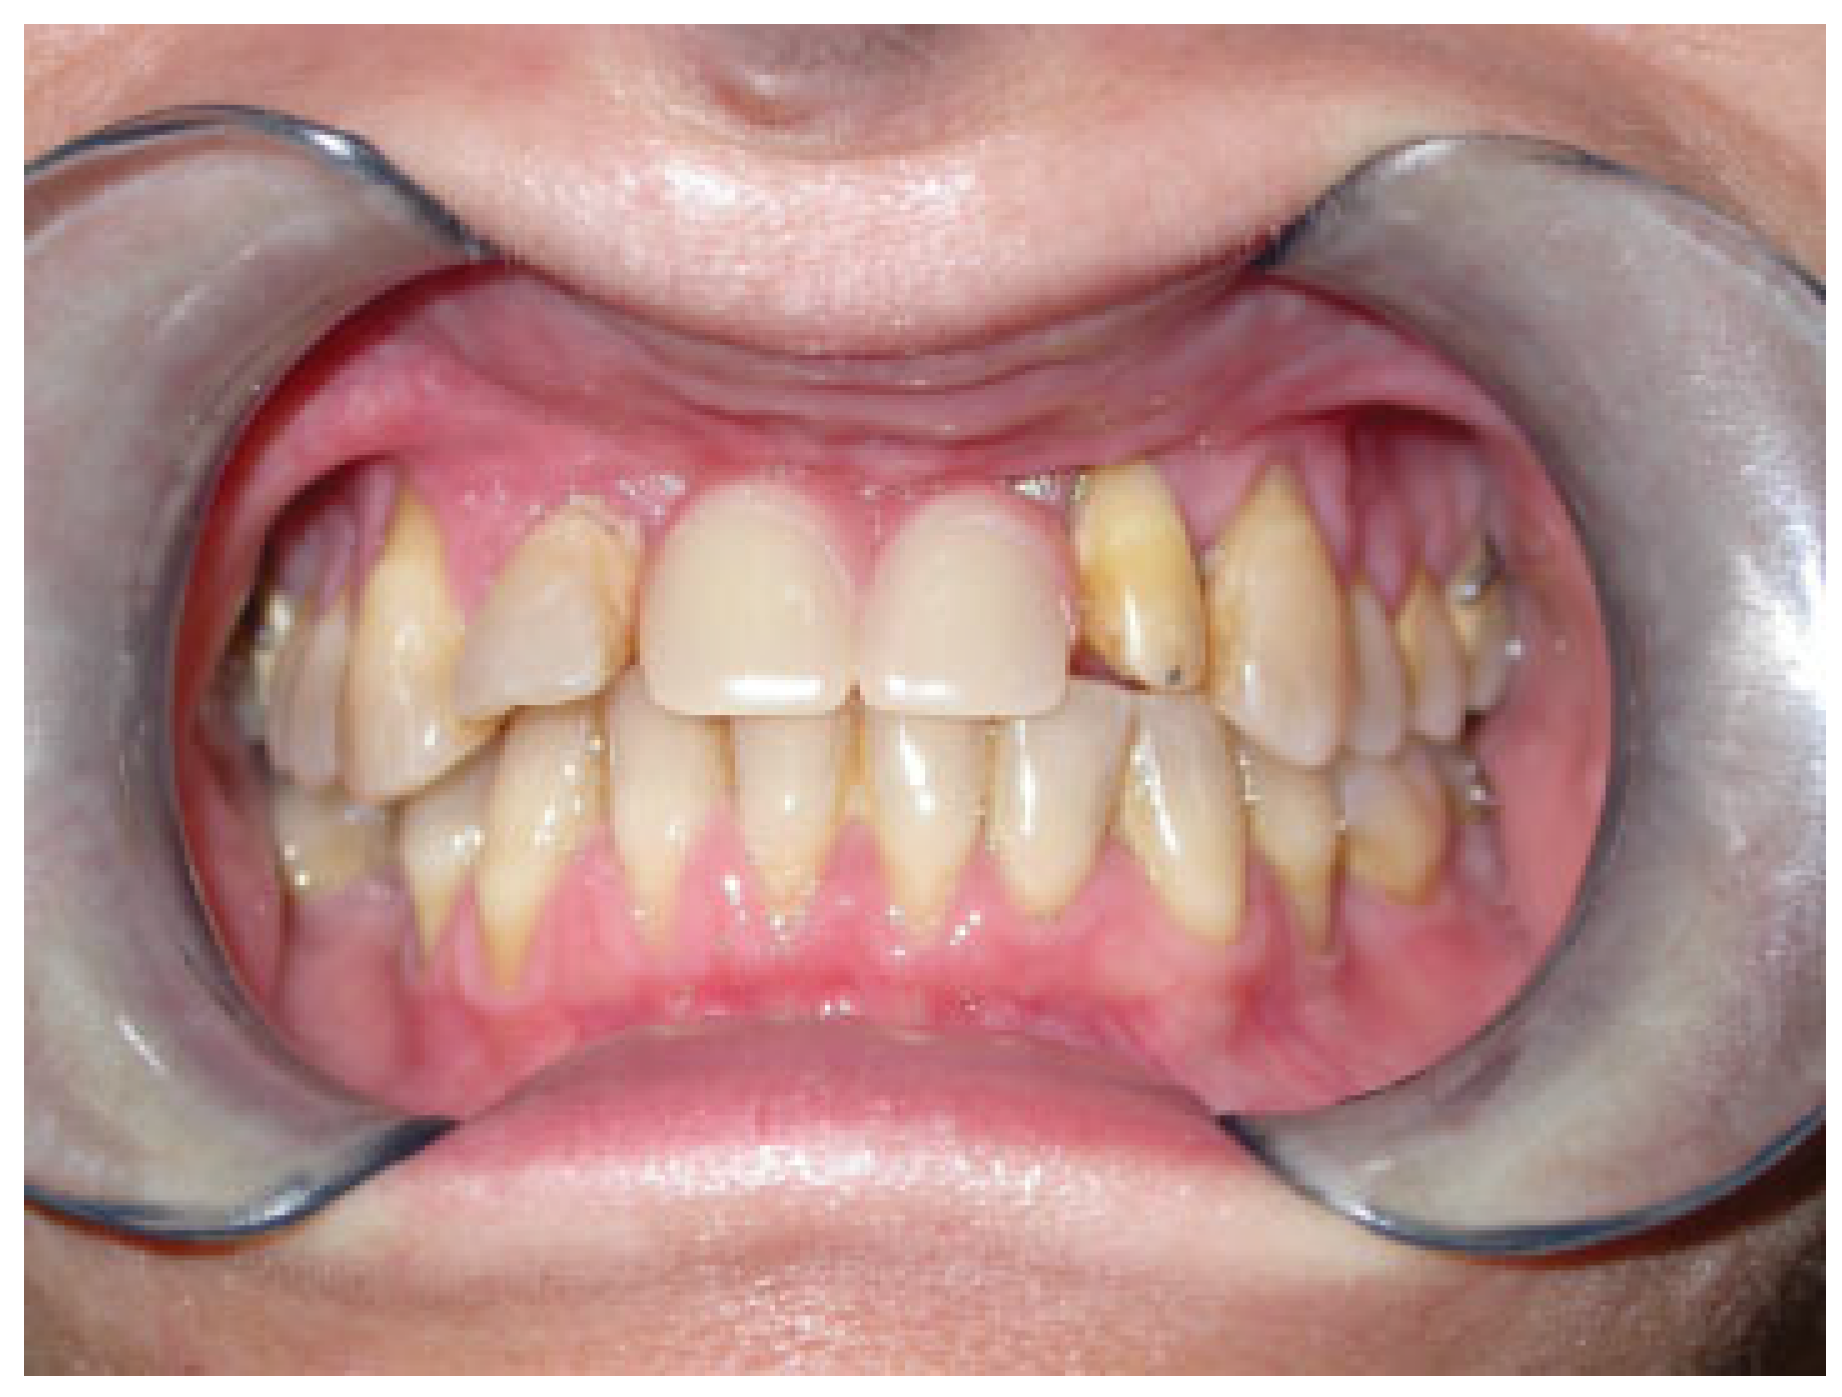

Figure 7.

Final intraoral view after dental implant rehabilitation.